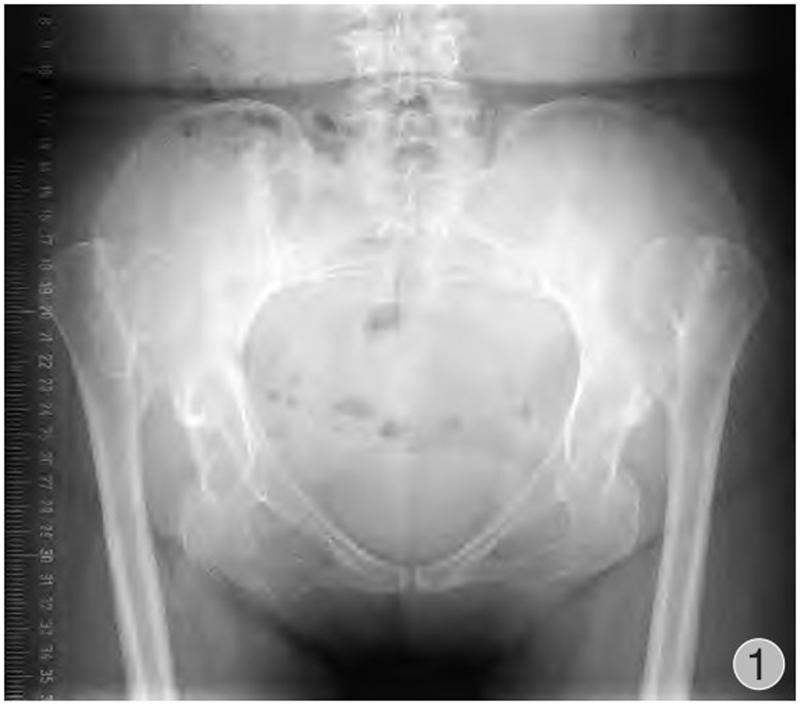

由于股骨头半脱位或脱位,发育中的真性髋臼缺乏应力刺激未能正常生长发育,骨性髋臼形成通常较小,多呈三角形,被软组织所覆盖,部分病例会有骨性覆盖以及骨性解剖标志丧失等(图1~3)。发育不良的髋臼往往较浅且前倾增大,前壁变薄,骨量不足,前后径减小,可有上方和(或)前方节段性缺损。根据是否存在假臼,有学者将Crowe Ⅳ型进一步分为Ⅳa(无假臼)和Ⅳb(有假臼),并提出假臼的存在是影响THA脱位高度和转子下截骨术应用的重要因素,HARTO等发现无假臼的高脱位DDH患者THA术后假体存留率不及有假臼形成患者,并且假臼的存在与否影响近端股骨的应力传导并可能与近端股骨形态有关,因此包含形态分类的术前规划是有必要的。如何寻找真臼的位置以及髋臼杯的安放是手术成功的关键。

图2 术前髋关节CT三维重建(右侧观):股骨头脱位高度>股骨头高度的100%,真臼未能正常发育,髋臼浅小呈三角形,前倾增大,前后柱骨质丰厚,无大量骨缺损;右侧股骨头小,股骨颈短,颈干角、偏心距减小,股骨头与髂骨翼未形成假臼,股骨近端骨皮质变薄,髓腔窄小变直,呈柱状